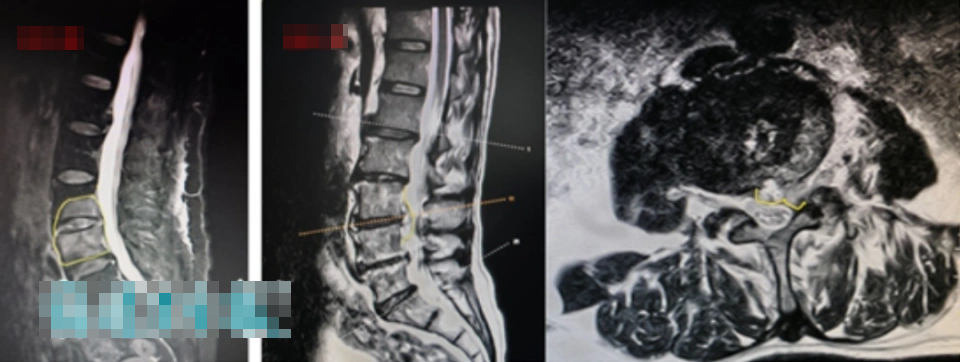

Sau khi tham khảo ý kiến chi tiết và khám sức khỏe, bác sĩ đã đưa ra chẩn đoán sơ bộ rằng cả hai người có thể mắc bệnh viêm cột sống liên quan đến bệnh Brug. "Các mẫu máu được lấy để xét nghiệm, và các kiểm tra liên quan như chụp cộng hưởng từ (MRI) cũng được thực hiện".

Vài ngày sau, kết quả xét nghiệm đã có - cả hai vợ chồng đều “dương tính với kháng thể brucellosis”; chụp cộng hưởng từ (MRI) cũng cho thấy có dấu hiệu viêm rõ ràng ở các khoảng gian đốt sống và các đốt sống liền kề của cột sống thắt lưng.

Trong đó, tình trạng của chồng bà Trương nghiêm trọng hơn: cột sống thắt lưng của ông không chỉ bị nhiễm trùng mủ mà tình trạng viêm nhiễm còn lan vào ống sống, khiến cột sống thắt lưng của ông trở nên vô cùng không ổn định. Ông có nguy cơ gặp phải những hậu quả nghiêm trọng như tê liệt và đau nhức ở chân, yếu cơ, thậm chí là liệt toàn thân và tiểu không tự chủ bất cứ lúc nào.

"Vì xương và đĩa đệm cột sống thắt lưng đã bị vi khuẩn 'ăn mòn', và ổ áp xe đã xâm lấn vào ống sống, nên trước tiên chúng tôi cần loại bỏ các tổn thương nhiễm trùng cho cặp vợ chồng này, sau đó cấy ghép xương sạch vào vùng xương bị khuyết. Chỉ sau khi xương lành hoàn toàn thì sự ổn định của cột sống thắt lưng mới được phục hồi". Các bác sĩ đã thực hiện phẫu thuật "loại bỏ tổn thương nhiễm trùng cột sống thắt lưng + ghép xương + cố định nội tủy bằng vít chân cuống" cho cặp vợ chồng này.